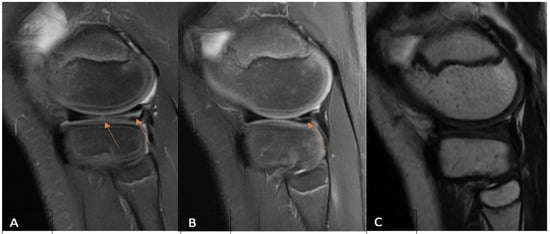

2.2. MRI Evaluation Protocol